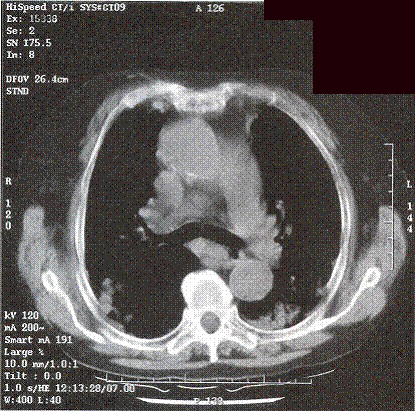

Initially, she was treated as community acquired pneumonia. However her symptom did not improve and she got persistent low-grade fever. CXR showed even more extensive shadow. Bronchoscopy was performed but no endobronchial lesion was found. Transbronchial biopsy was taken from left lingular lobe showed non-specific inflammation. Neither malignant cell nor acid-fast bacilli was found. CT thorax (Fig 3 & 4) was performed which showed widespread ill-defined patchy and nodular opacities and small reactive mediastinal lymph node. CT guided fine-needle aspiration of lung opacity was perfonned but material obtained was insufficient for diagnosis. Her general condition deteriorated despite multiple course of antibiotics treatment. She developed type 1 respiratory failure with oxygen dependency. Open lung biopsy was arranged but was withheld due to poor respiratory reserve. Another session of bronchoscopy was performed. This time the transbronchial biopsy showed evidence of diffuse alveolar damage. Her condition deteriorated further and became bed-ridden. On further questioning, amiodarone has been taken by patient for cardiac problem for few years and was stopped few months prior this admission due to bradycardia. Amiodarone pulmonary toxicity was suspected and oral prednisolone with a dose of Img/kg/day was started.